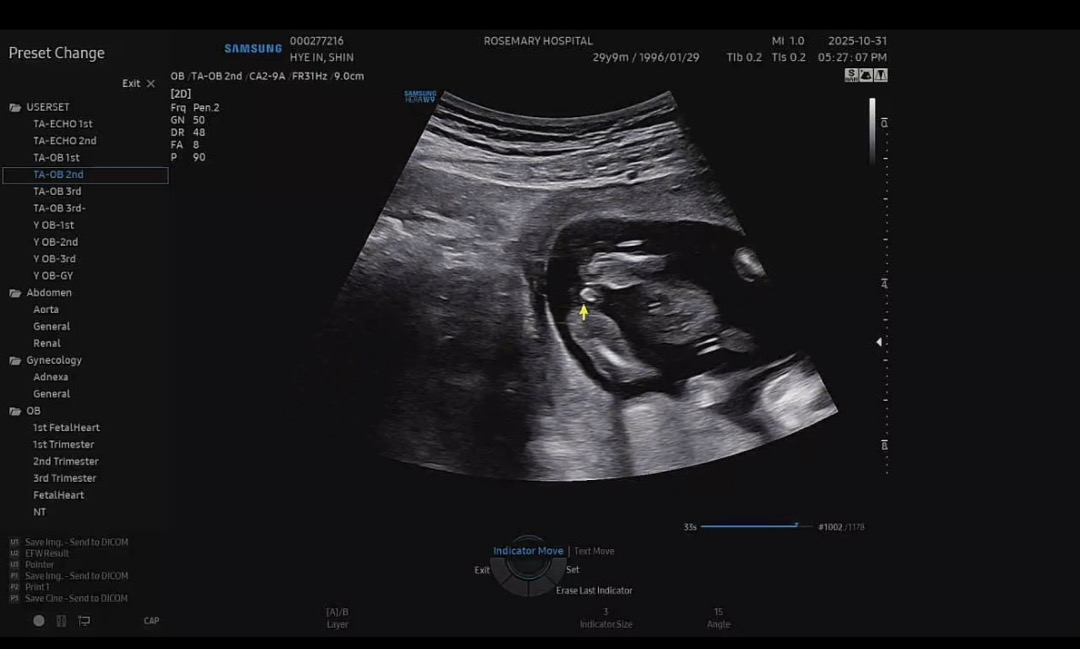

15주 3일 초음파 봐주세요!!!!!

생각보다 넘 일찍오셨다구 성별을 정확하게 안알려주시더라구요 ㅠㅠㅋㅋㅋ다들 보시기에 어때보이세요!!??

저오늘15주인데 아무리봐도 🌶️인지모르겠는데 보자마자 남자네요 했네요...🙂↕️